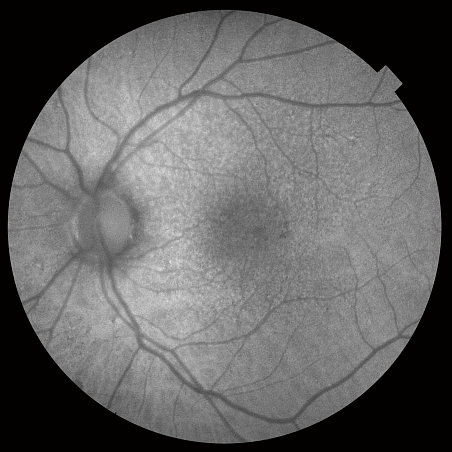

Помимо ОКТ и ОКТ-ангиографии прибор позволяет получить снимки глазного дна с помощью встроенной немидриатической фундус-камеры. Модель DRI TRITON plus оснащена также модулями флуоресцентной ангиографии (AF) и автофлуоресценции (FAF).

Уникальная система навигации позволяет определять локализацию каждого В-скана ОКТ на фундус-изображении и наоборот.